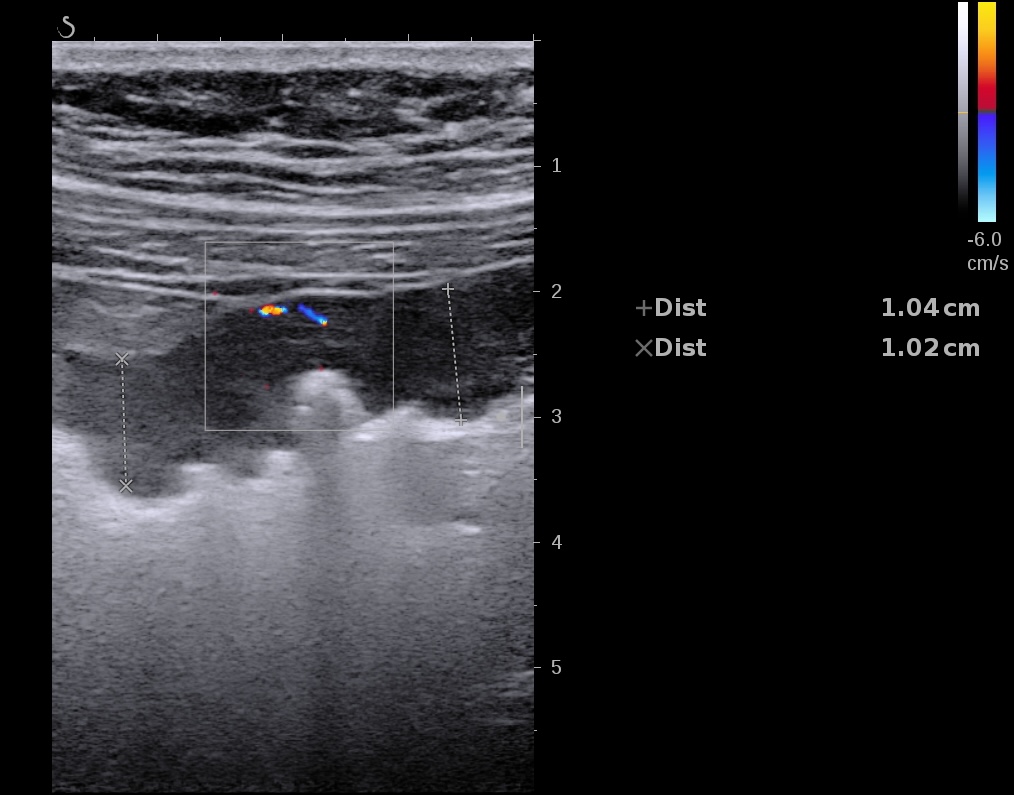

Echographie des cas numéro 2 puis 3

Epaississement entre 4.5 et 7 mm selon les segment, la structure en couche disparait totalement par endroit, à d’autre elle est partiellement conservée. Activité doppler intense de la paroi

Le Score de Milan (MUC) est à (1,4 x7+2) = 11,8

Là encore la paroi est très hypoéchogène, la structure en couches est par endroit totalement absente, ulcérations en surface, infiltration de la graisse, doppler intense, petites adénopathies périphériques.

Le rectum est bien vu avec la sonde basse fréquence la paroi atteint 10 mm à ce niveau.

Le score de Milan MUC est de (10 x1,4+2) = 16